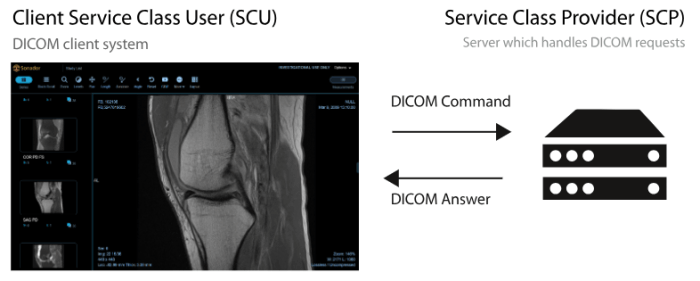

The DICOM PACS Server is a medical imaging software designed to store, retrieve, and distribute medical images and associated data in compliance with the DICOM standard.

Our PACS Server provides a lightweight, open-source solution with features such as DICOM networking, anonymization, query/retrieve capabilities, and support for various medical imaging modalities like X-ray, MRI, CT scans, etc. It's highly customizable, scalable, and can be integrated with other healthcare IT systems, making it a popular choice for managing medical image archives.

DICOM IMAGES VIEWER

The OHIF DICOM Viewer is a web-based medical imaging viewer designed to display and interpret DICOM (Digital Imaging and Communications in Medicine) images from various modalities such as X-ray, MRI, CT scans, etc.

It offers a user-friendly interface with advanced features for medical professionals to view, manipulate, and analyze medical images efficiently.

Key features includes :

multi-planar reconstruction, windowing, zooming, panning, measurement tools for distance and area calculations, annotations, image fusion, and support for 3D rendering.

The viewer is highly customizable and can be integrated with other healthcare systems, enabling seamless access to patient imaging data across different platforms.